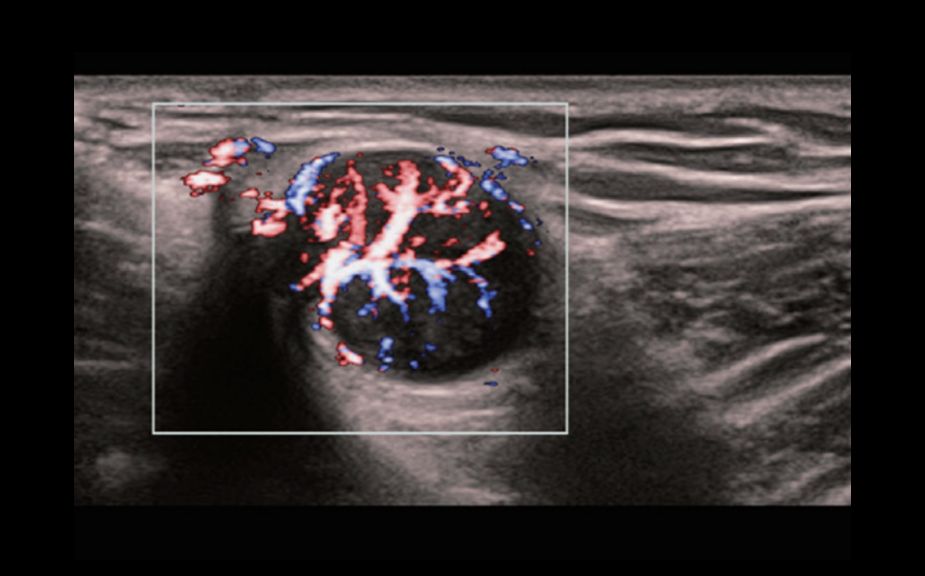

Новейший подход к изучению сосудистой гемодинамики: V Flow

Используются маркированные цветом вектора для индикации значения скорости и направления движения клеток крови. Благодаря сверхвысокой частоте кадров V Flow обеспечивает чрезвычайно четкую, точную и независимую от угла комплексную оценку сосудистой гемодинамики с возможностью всестороннего анализа.

V Flow

Новейший подход к изучению сосудистой гемодинамики: V Flow

Используются маркированные цветом вектора для индикации значения скорости и направления движения клеток крови. Благодаря сверхвысокой частоте кадров V Flow обеспечивает чрезвычайно четкую, точную и независимую от угла комплексную оценку сосудистой гемодинамики с возможностью всестороннего анализа.

V Flow